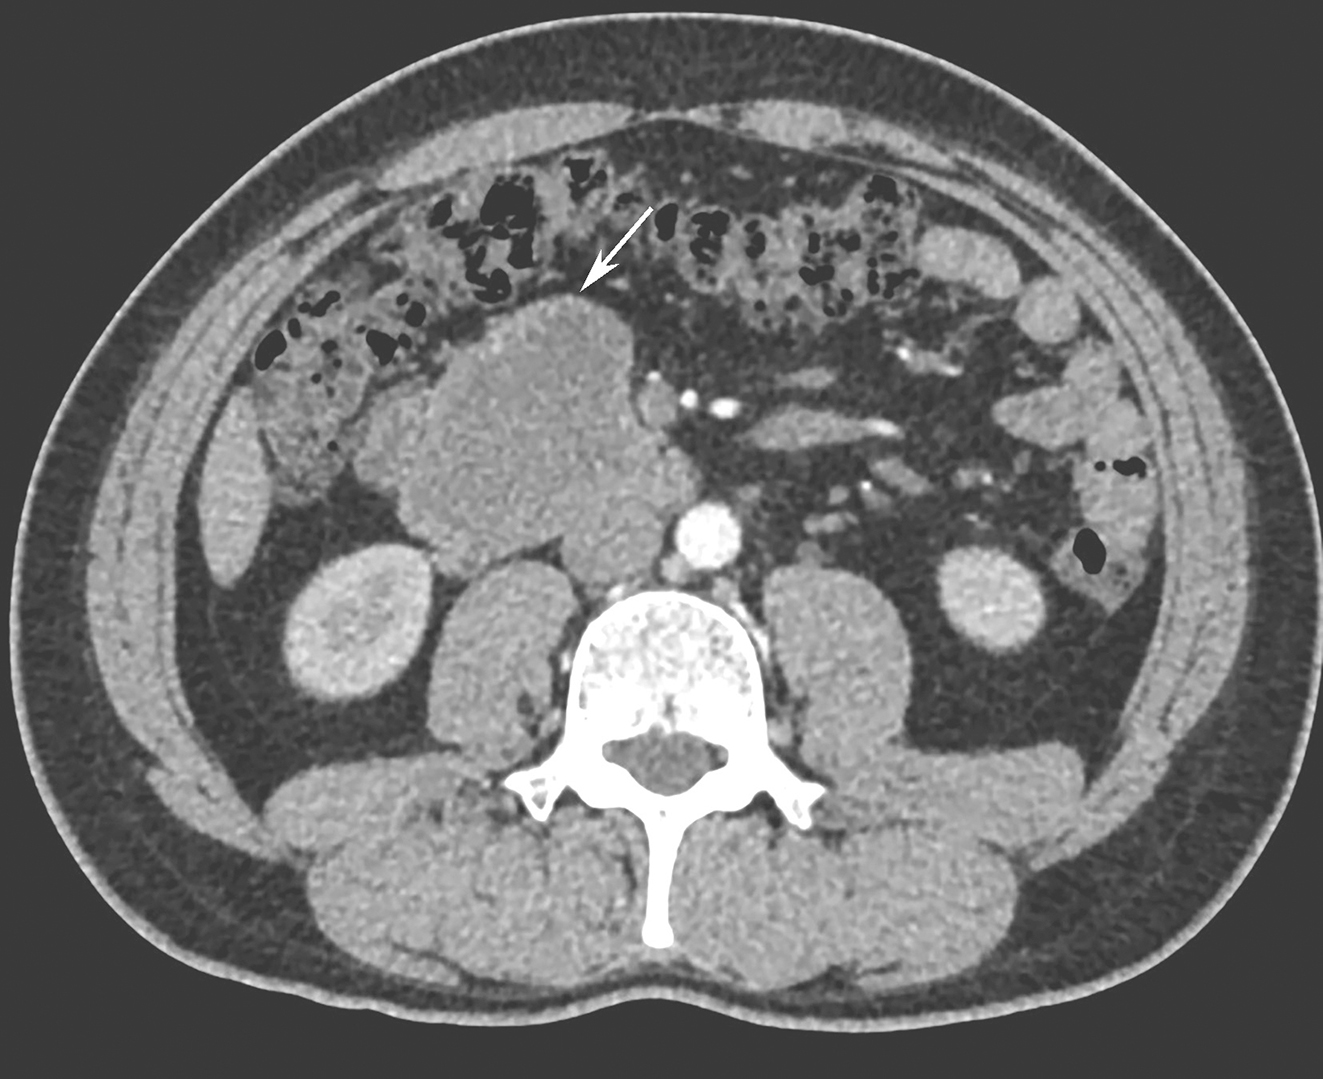

服药4个月后,2018年3月复查全腹增强CT示:十二指肠降部见等密度肿块影并向外生长,大小约6.6cm×5.1cm(图2),病灶边界尚清,与胰腺钩突、下腔静脉毗邻;中央见不规则液体密度影,肝固有动脉分支向病灶供血,邻近肠系膜根部多发小淋巴结;增强扫描示边缘实性成分可见强化,中心区域低密度影区未见明显强化;上述所见考虑胃肠间质瘤,较前病灶缩小;余所见较前片相仿。

图2 2018年3月全腹增强CT